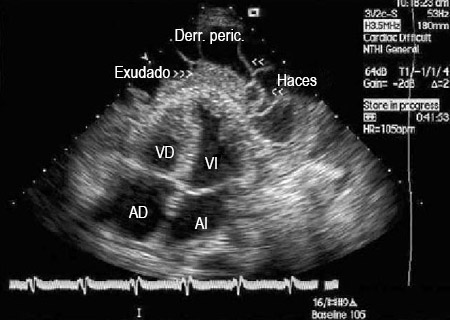

Vista apical de 4 cámaras de un ecocardiograma 2-dimensional de un paciente con derrame pericárdico tuberculoso; AI = aurícula izquierda, VI = ventrículo izquierdo, Derr. per.= derrame pericárdico; AD = aurícula derecha, VD = ventrículo derecho

De: George S, Salama AL, Uthaman B, et al. Heart. 2004; 90:1338-1339